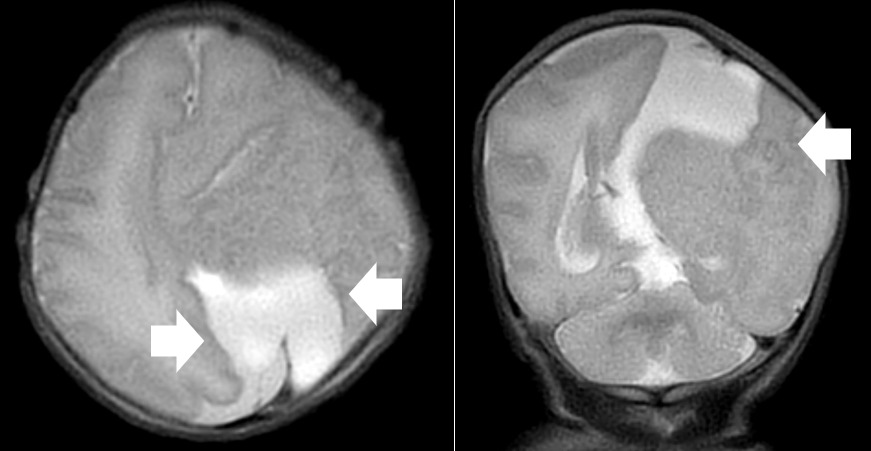

A repeat MRI on day-of-life 1 revealed multiple intracranial anomalies including extensive polymicrogyria of the left cerebral hemisphere, polymicrogyria in the right frontal lobe, incomplete development of the left lateral ventricle, and a gray matter lined cerebrospinal fluid cleft in the left posterior-frontal and parietal regions communicating with the rudimentary left lateral ventricle (Figures 5-7). The dysplastic left cerebral hemisphere exerted a mass effect on the rudimentary left lateral ventricle with a left-to-right midline shift measuring approximately 6 mm at the level of the foramen of Monroe. There was evidence of partial fusion of the frontal lobes. In summary, the first postnatal MRI confirmed that rather than a growing neoplasm, Twin A had extensive intracranial developmental anomalies, including a dysplastic left cerebral cortex, schizencephaly, and hypoplasia or absence of multiple midline structures.